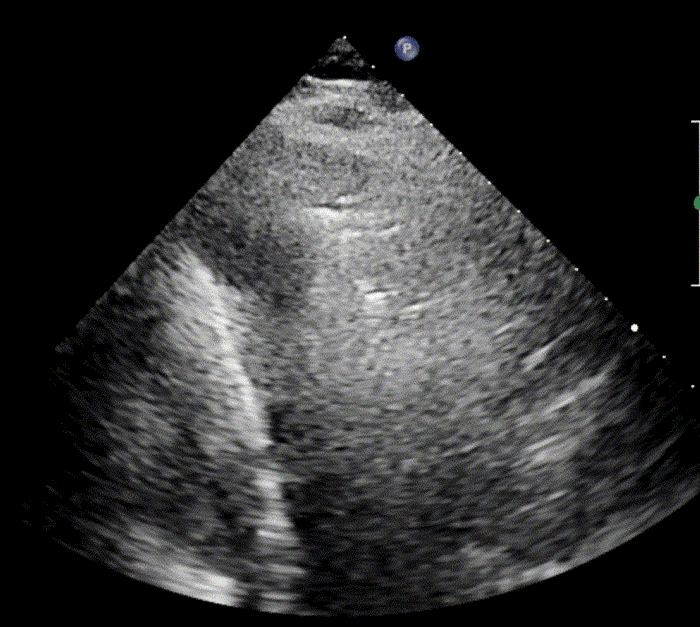

In healthy, air-filled lungs, the ultrasound image appears gray. This occurs because air scatters sound waves as they encounter solid interfaces such as the pleura, resulting in a diffuse, speckled gray appearance beneath it. Within normal lung parenchyma, there is minimal acoustic impedance mismatch to reflect the ultrasound beam; instead, the beam is absorbed by air within the alveoli. Consequently, in a normal lung ultrasound, the parenchymal texture is not visualized. The only visible structure is the pleural line — a bright, horizontal echo that moves synchronously with respiration.

A-lines

A-lines are highly echogenic, horizontal reverberation artifacts that appear parallel to and equidistant beneath the pleural line. They result from repetitive reflection of the ultrasound beam between the pleura and the probe, producing regularly spaced bright lines on the image.

The presence of A-lines indicates a normally aerated, air-filled lung. They are typically observed when imaging at a depth of 9–11 cm, and are most distinct when the ultrasound beam is perpendicular to the pleural surface.